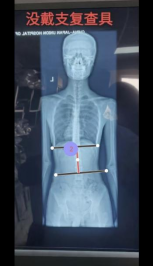

案例3:患者,13岁,青少年特发性脊柱侧弯。考虑其尚处发育期,需兼顾矫正与生活质量的需求,我科室应用3D打印个性化矫形器进行治疗,通过三维扫描获取患者躯干精准数据,经生物力学模拟设计后,3D打印出轻量化、透气且完全贴合的个性化矫形器,不仅实现了显著的即时矫正效果、有效控制了侧弯进展,更凭良好的佩戴舒适度提升了患者依从性。该技术以最小的负担,护航青少年患者的脊柱健康与正常成长,意味着医院逐步形成了脊柱侧弯手术与非手术的完整治疗体系。